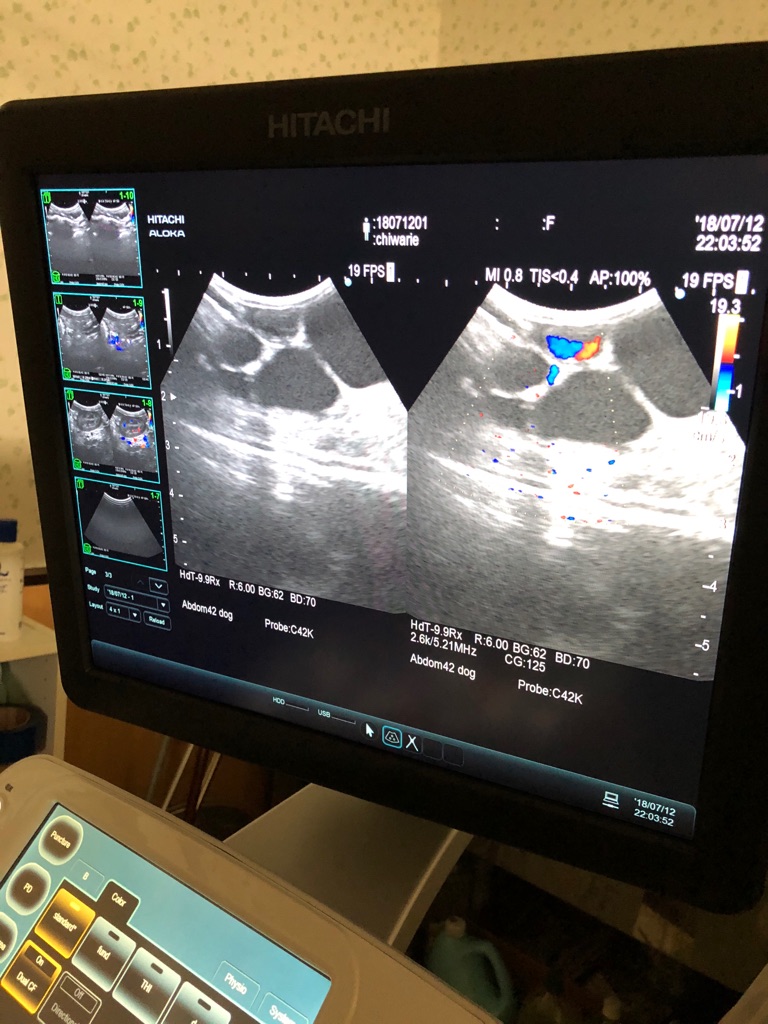

この画像のチワワのお母さんも 先程のエコーで子宮蓄膿症がわかりました、

ヘルニアも、腫瘍も有ります、手術しなければ蓄膿が破裂し腹膜炎で苦しんで亡くなります、

先生は早急に手術の予定を立てて下さるそうですので安心しました。